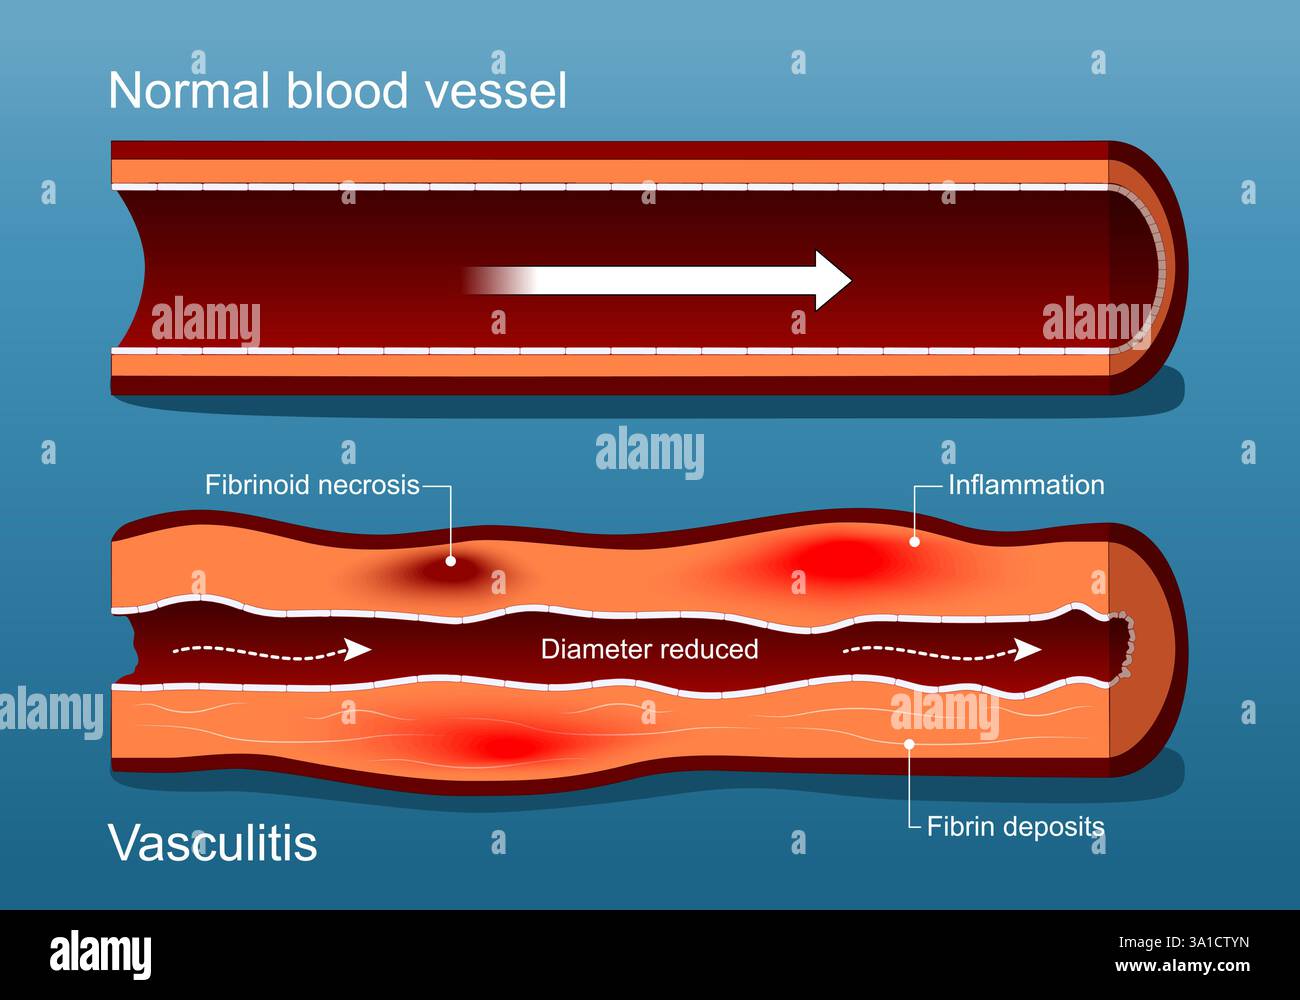

Vasculitis. Autoimmune disease. Healthy Blood vessel and Vascular damage with Diameter reduced, Inflammation, Fibrin deposits and Fibrinoid necrosis. Stock Vectorhttps://www.alamy.com/image-license-details/?v=1https://www.alamy.com/vasculitis-autoimmune-disease-healthy-blood-vessel-and-vascular-damage-with-diameter-reduced-inflammation-fibrin-deposits-and-fibrinoid-necrosis-image654891657.html

Vasculitis. Autoimmune disease. Healthy Blood vessel and Vascular damage with Diameter reduced, Inflammation, Fibrin deposits and Fibrinoid necrosis. Stock Vectorhttps://www.alamy.com/image-license-details/?v=1https://www.alamy.com/vasculitis-autoimmune-disease-healthy-blood-vessel-and-vascular-damage-with-diameter-reduced-inflammation-fibrin-deposits-and-fibrinoid-necrosis-image654891657.htmlRF3A1CTYN–Vasculitis. Autoimmune disease. Healthy Blood vessel and Vascular damage with Diameter reduced, Inflammation, Fibrin deposits and Fibrinoid necrosis.